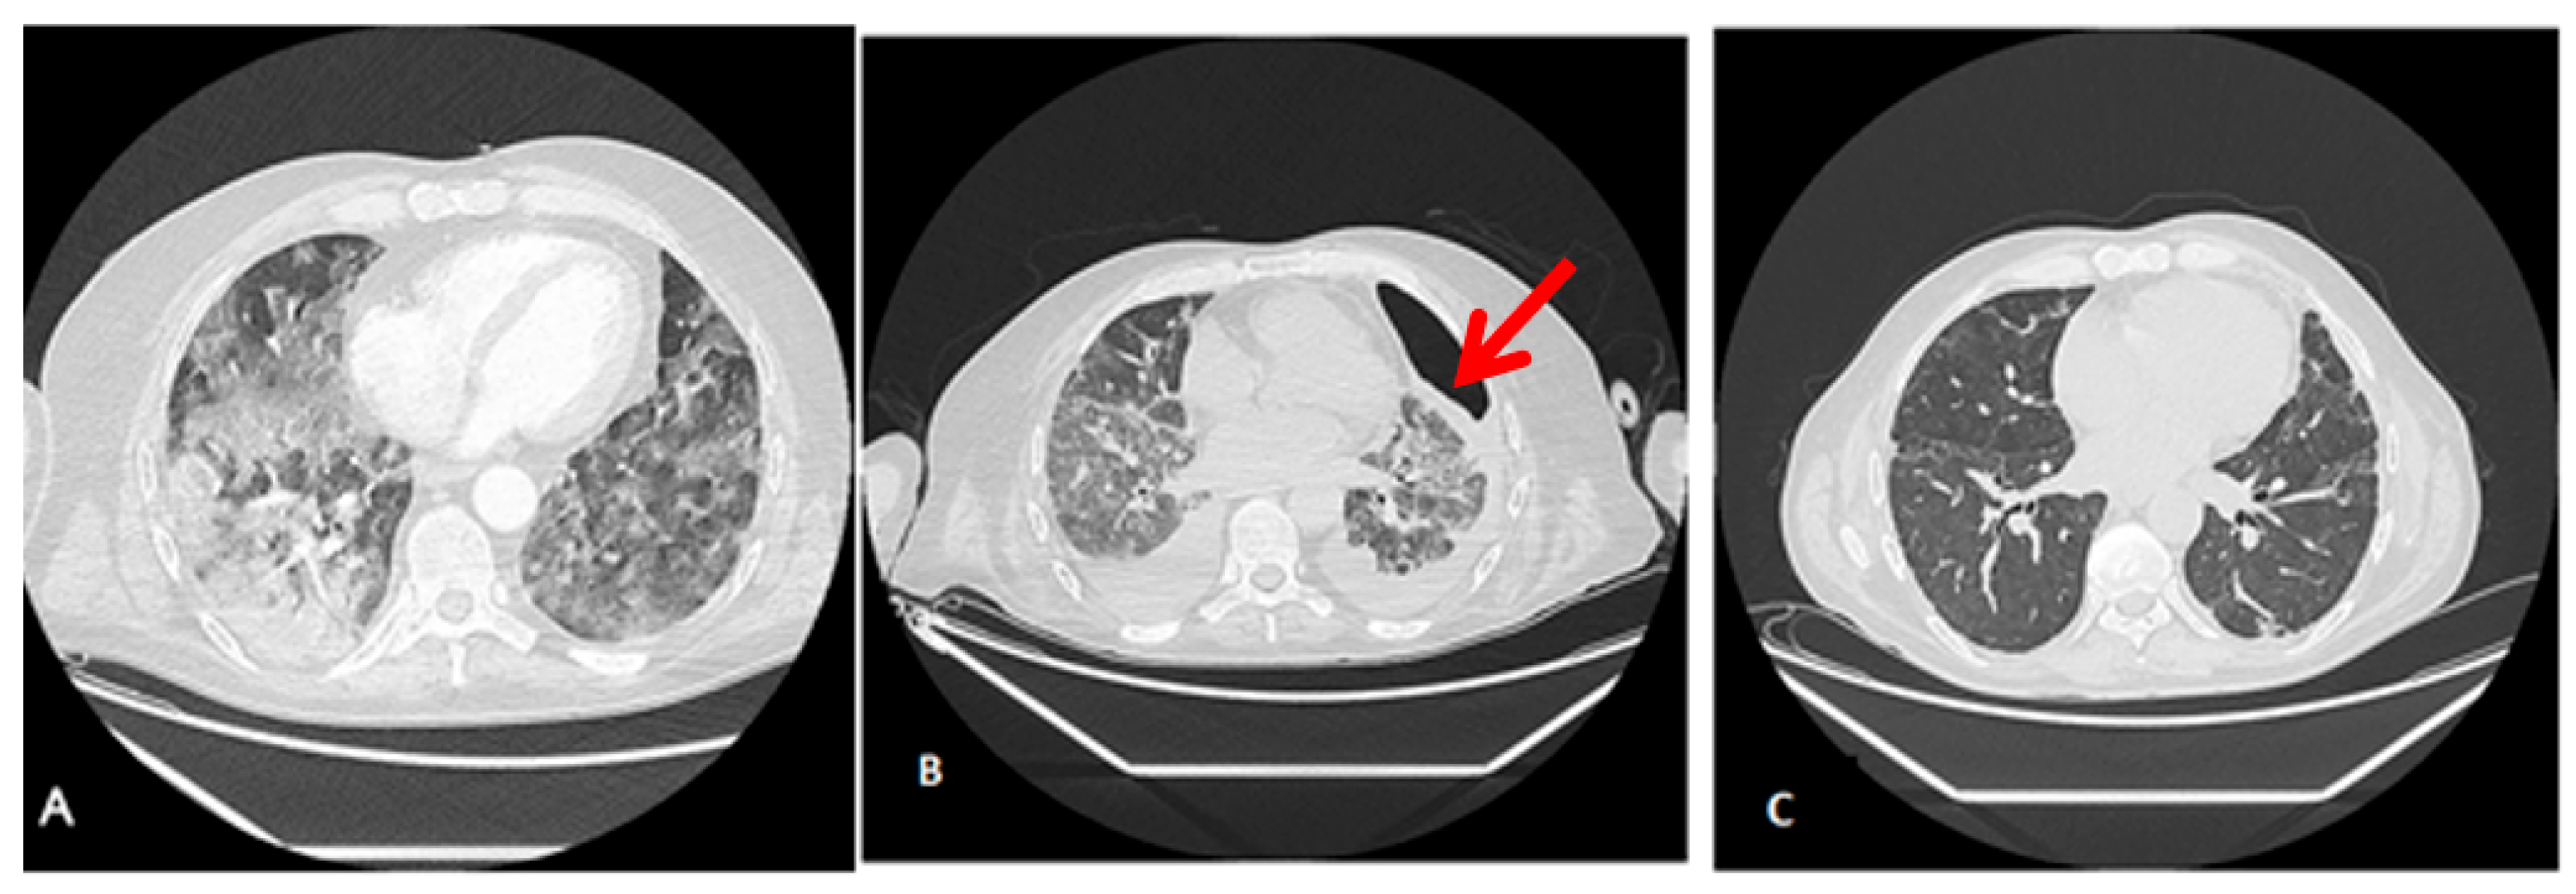

Figure 1 shows thoracic computerized axial tomography of case 1 (polytrauma with persistent air leak after thoracic drainage) before ECCO2R treatment at day 42 after ICU admission (A) and 10 days after ECCO2R treatment at day 55 of ICU admission (B).

Radiological findings of case 1 ((A). Day 42 after ICU admission, before ECCO2R treatment (B). After 10 days ECCO2R treatment. Day 55 after ICU admission). Case #1: Thoracic computerized axial tomography that shows bilateral alveolar condensations affecting all lung lobes indicating a significant radiological worsening. Bilateral pleural effusion of up to 22 mm in the right hemithorax and 30 mm in the left one (red arrows). An intraparenchymal bubble (blue arrow) of approximately 30 by 26 mm is observed in the anterior basal segment of the right lower lobe, which does not allow abscessification to be ruled out (A). After ECCO2R therapy (B), it should be acknowledged that the radiologic improvement could also be an effect of the improvement in the disease.

Radiological findings of case 2 (esophageal surgery [Ivor–Lewis esophagectomy] with iatrogenic bronchopleural and esophageal fistulous hole) are shown in Figure 2. The computer axial tomography (CAT) shows atelectasis of the right lower pulmonary lobe with left posterolateral passive atelectasis at admission (Figure 2A) and at discharge after endobronchial prothesis and ECCO2R therapy (Figure 2B)

Radiological findings of case 2. Case #2: (A): The computed axial tomography (CAT) scan shows an atelectasis of the right lower pulmonary lobe with discrete bilateral pleural effusion, predominantly right, partially encapsulated. Mild left pleural effusion with left posterolateral passive atelectasis. (B): CAT at discharge, 20 days after ICU admission, after endobronchial prothesis and ECCO2R therapy. It should be taken into account that radiological findings improvement may be due to pathology resolution (fistulous hole).